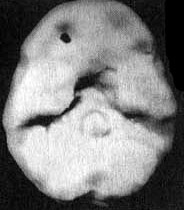

Нормальный мозг

Иллюстрация к книге — Измените свой мозг - изменится и жизнь! [i_004.jpg]